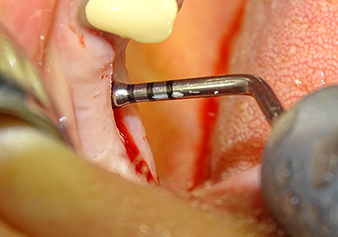

Après un contrôle intermédiaire (Fig. 4), une étape de préparation ultérieure est exécutée (Fig. 5). Puis on utilise l’insert Z35P hydraulique pour relever la membrane vers la position souhaitée (Fig. 6 et 7). Ensuite, une préparation piézochirurgicale supplémentaire est pratiquée sur le site implantaire, en utilisant pour terminer un burin rotatif et une fraise à épaulement jusqu’à 4,8 mm de diamètre d'implant. Avant l’insertion de l'implant, le matériau d’augmentation (taille de particules env. 0,8-1,6 mm) est introduit sous la membrane de Schneider (Fig. 8).